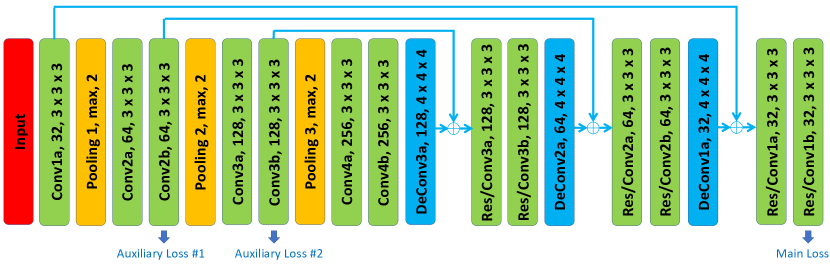

Network Architecture

As shown in Fig. 3, we provide an illustration of our convolutional network architecture. Inspired by V-Net milletari2016v , 3D U-Net cciccek20163d , and VoxResNet chen2017voxresnet , we have an encoder path followed by a decoder path each with four resolution steps. The left part of network acts as a feature extractor to learn higher and higher level of representations while the right part of network decompresses compact features into finer and finer resolution to predict the per-voxel segmentation. The padding and stride of each layer (Conv, Pooling, DeConv) are carefully designed to make sure the densely predicted output is the same size as the input.

The encoder sub-network on the left is divided into different steps that work on different resolutions. Each step consists of one to two convolutions, where each convolution is composed of convolution followed by a batch normalization (BN ioffe2015batch ) and a rectified linear unit (ReLU nair2010rectified ) to reach better convergence, and then a max pooling layer with a kernel size of and strides of two to reduce resolutions and learn more compact features. The downsampling operation implemented by max-pooling can reduce the size of the intermediate feature maps while increasing the size of the receptive fields. Having fewer size of activations makes it possible to double the number of channels during feature aggregation given the limited computational resource.

The decoder sub-network on the right is composed of several steps that operate on different resolutions as well. Each step has two convolutions with each one followed by a BatchNorm and a ReLU, and afterwards a Deconvolution with a kernel size of and strides of two is connected to expand the feature maps and finally predict the segmentation mask at the last layer. The upsampling operation that is carried out by deconvolution enlarges the resolution between each step, which increases the size of the intermediate activations so that we need to halve the number of channels due to the limited memory of the GPU card.

Apart from the left and right sub-networks, we impose a residual connection he2016deep to bridge short-cut connections of features between low-level layers and high-level layers. During the forward phase, the low-level cues extracted by networks are directly added to the high-level cues, which can help elaborate the fine-scaled segmentation, e.g., small parts close to the boundary which may be ignored during the feature aggregation due to the large size of receptive field at high-level layers. As for the backward phase, the supervision cues at high-level layers can be back-propagated through the short-cut way via the residual connections. This type of mechanism can prevent networks from gradient vanishing and exploding glorot2010understanding , which hampers network convergence during training.

We have one mainstream loss layer connected from “Res/Conv1b” and another two auxiliary loss layers connected from “Conv2b” and “Conv3b” to the ground truth label, respectively. For the mainstream loss in “Res/Conv1b” at the last layer which has the same size of data flow as one of the input, a convolution is followed to reduce the number of channels to the number of label classes which is in our case. As for the two auxiliary loss layers, deconvolution layers are connected to upsample feature maps to be the same as input.

The deep supervision imposed by auxiliary losses provides robustness to hyper-parameters choice, in that the low-level layers are guided by the direct segmentation loss, leading to faster convergence rate. Throughout this work, we have two auxiliary branches where the default parameters are and in Eq. 3 to control the importance of deep supervisions compared with the major supervision from the mainstream loss for all segmentation networks.

As shown in Table 1, we give the detailed comparisons of network configurations in terms of four aspects: long residual connection, short residual connection, deep supervision and loss function. Our backbone network architecture, named as “ResDSN”, is proposed with different strategies in terms of combinations of long residual connection and short residual connection compared with VoxResNet chen2017voxresnet , 3D HED merkow2016dense , 3D DSN dou20173d and MixedResNet yu2017volumetric . In this table, we also depict “FResDSN” and “SResDSN”, where “FResDSN” and “SResDSN” are similar to MixedResNet yu2017volumetric and VoxResNet chen2017voxresnet , respectively. As confirmed by our quantitative experiments in Sec. 4.1, instead of adding short residual connections to the network, e.g., “FResDSN” and “SResDSN”, we only choose the long residual element-wise sum, which can be more computationally efficient while even performing better than the “FResDSN” architecture which is equipped with both long and short residual connections. Moreover, ResDSN has noticeable differences with respect to the V-Net milletari2016v and 3D U-Net cciccek20163d . On the one hand, compared with 3D U-Net and V-Net which concatenate the lower-level local features to higher-level global features, we adopt the element-wise sum between these features, which outputs less number of channels for efficient computation. On the other hand, we introduce deep supervision via auxiliary losses into the network to yield better convergence.